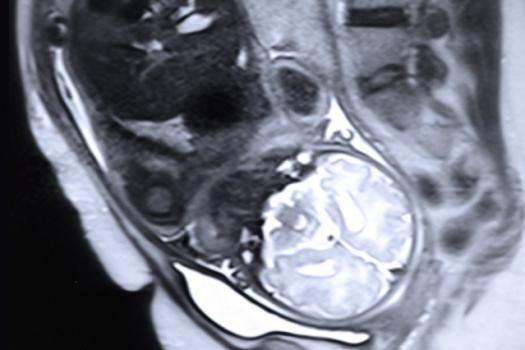

A team led by Polina Golland’s group at MIT’s Computer Science and Artificial Intelligence Laboratory has made a new algorithm for identifying organs in fetal MRI scans, which should make MRI monitoring much more useful. Pictured is a stock image of a fetal MRI.

And at the International Conference on Medical Image Computing and Computer Assisted Intervention this week, a team led by Polina Golland’s group at MIT’s Computer Science and Artificial Intelligence Laboratory presented a paper demonstrating a new algorithm for tracking organs through sequences of MRI scans, which will make MRI monitoring much more useful.